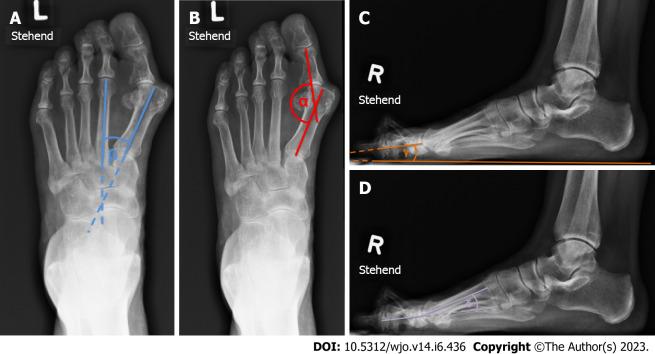

Between September 2011 and November 2020 a total 72 of MTP1 fusions were performed using a low profile, pre-contoured dorsal locking plate and a plantar compression screw. Union and revision rates were analyzed with a minimum clinical and radiological follow up of at least 3 mo (range 3-18 mo). The following parameters were evaluated on pre- and postoperative conventional radiographs: Intermetatarsal angle, Hallux-valgus angle, dorsal extension of the proximal phalanx (P1) in relation to the floor and the angle between the Metatarsal 1 and the P1 (MT1-P1 angle). Descriptive statistical analysis was performed. Pearson analysis was used to assess for correlations between radiographic parameters and achievement of fusion.

RESULTS

An overall union rate of 98.6% (71/72) was achieved. Two out of 72 patients did not primarily fuse with one patient suffering from a non-union, whilst the other demonstrating a radiological delayed union without clinical symptoms, with eventually complete fusion after 18 mo. There was no correlation between the measured radiographic parameters and the achievement of fusion. We believe the reason for the non-union was mainly attributed to the patient's incompliance without wearing the therapeutic shoe leading to a fracture of the P1. Furthermore, we didn`t find any correlation between fusion and the degree of correction.